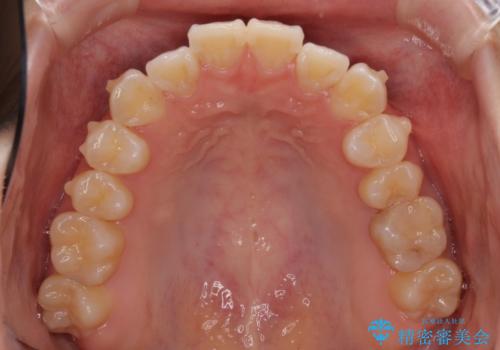

年に一度、夏休みの時期にしか帰国できないため、帰国のタイミングに合わせてマウスピース交換スケジュール治療計画としたため、3年半という期間を要しました。

留学先でもしっかりとマウスピースの装着を実践してくださったので、ご本人の満足のいく仕上がりとなりました。